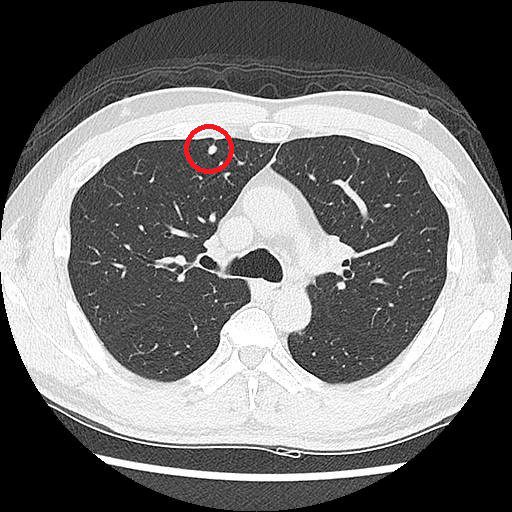

LDCT影像顯示,黃先生的右上肺處有一約0.5公分的結節,因無高度惡性特徵,僅需定期追蹤。

低劑量電腦斷層(LDCT)在肺癌的篩檢日漸普及,但篩檢出微小結節後是否需要切除,也成為許多人的疑問。對此,台北慈濟醫院胸腔外科陳東仁醫師指出,肺結節不等於肺癌,更不代表一定要立刻開刀,臨床上會依照病灶大小、型態、位置及變化綜合判斷。加上肺癌治療已朝向精準醫學發展,對於部分位置或大小難以掌握的肺部病灶,可以透過術前電腦斷層染色定位或螢光定位,盡量縮小切除範圍,保留更多正常肺葉與肺功能。以61歲黃先生為例,戒菸一段時間的他主動接受LDCT篩檢後,發現右上肺有一顆約0.5公分的肺部結節,考量影像沒有高度惡性特徵,陳醫師安排他持續追蹤觀察,若有變大趨勢再進一步討論醫療方針。